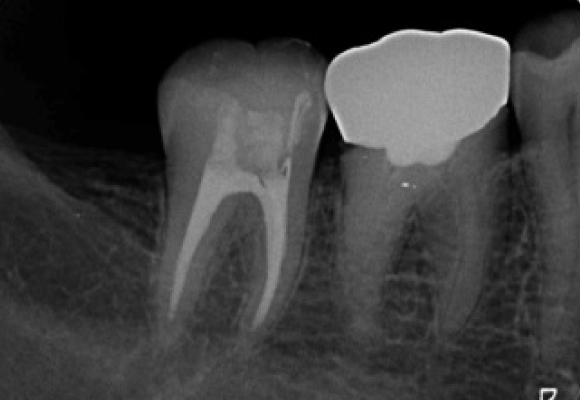

エックス線検査

歯周病治療後被せ物をしっかりフィットさせることで歯周病の再発を防ぎます。

治療前(症例)

治療後(症例)

治療前、被せ物と冠の間に段差がありフィットしていませんが、歯周病治療後しっかりと被せ物をフィットできています。